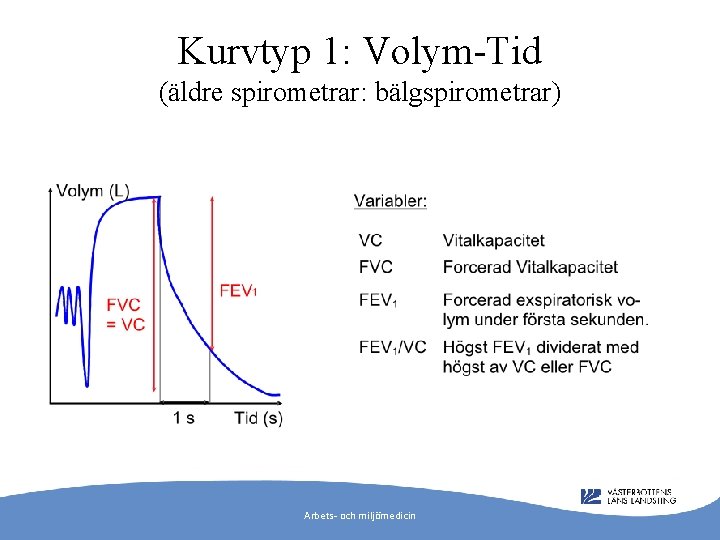

Kurvtyp 1: Volym-Tid (äldre spirometrar: bälgspirometrar) Arbets- och miljömedicin

Vad behövs för tolkning? • • VC (vitalkapacitet) FVC (forcerad vitalkapacitet) FEV 1 (forcerad ensekundsvolym) FEV% (FEV 1/VC eller FVC) Arbets- och miljömedicin